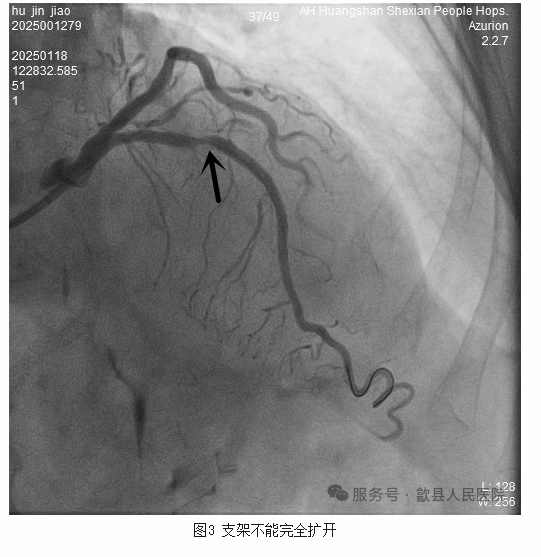

于是手术团队立即在延长导管辅助下成功植入1枚2.5*36mm的支架。但术后造影可见支架部分扩张不完全。虽多次尝试支架内球囊后扩张,钙化环却像“紧箍咒”一样牢牢地勒住支架(图3)。

支架不能完全扩张,短期内可导致急性支架内血栓。远期则导致支架内再狭窄,不利于患者预后。心血管内科主任、俞志雄副主任医师想到目前最有效的处理策略便是使用冲击波球囊打开钙化环。